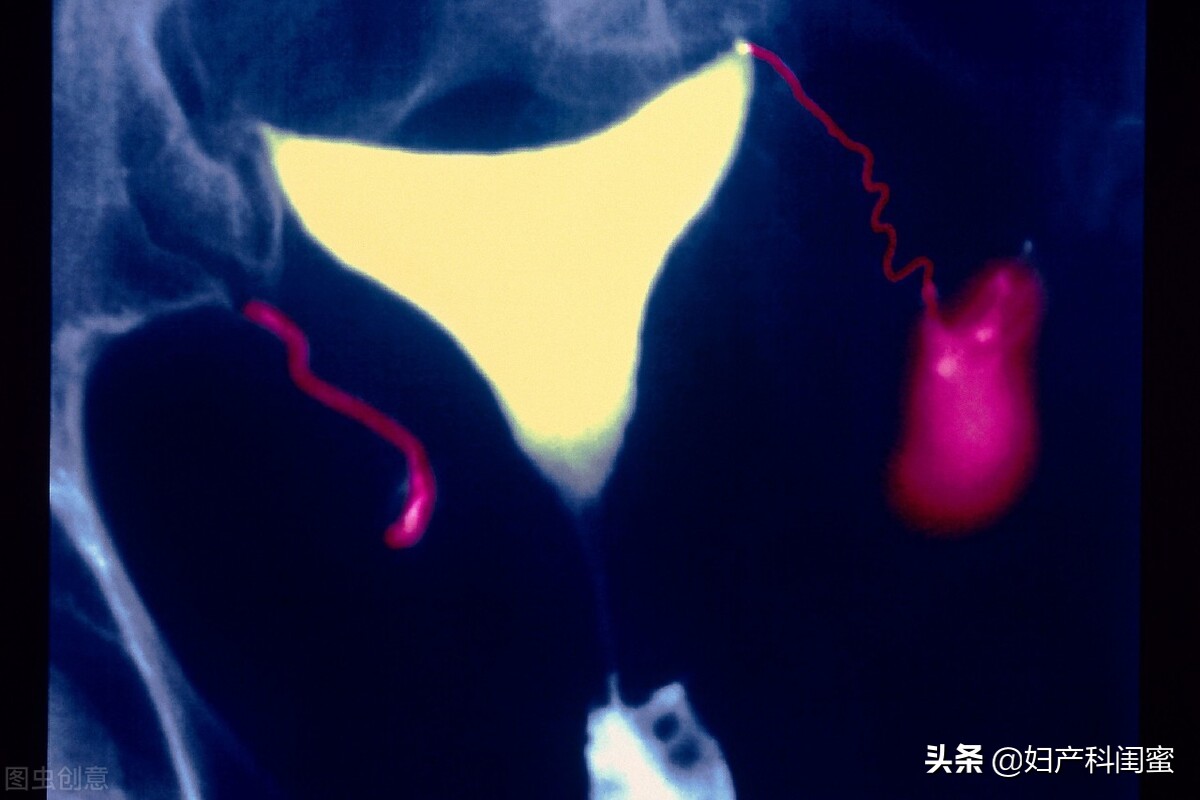

4、子宫输卵管数字减影血管造影术 可动态显示子宫、输卵管形态及梗阻部位,并DSA 引导下阻塞输卵管再通术。即可明确诊断,根据其病变性质进行治疗,可使一部分不孕患者的输卵管再通而受孕。但技术、设备要求高,费用高,创伤性操作易出现输卵管穿孔。